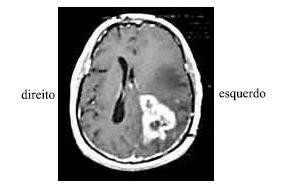

Uma senhora de 55 anos de idade, viúva, diabética e hipertensa, deu entrada no pronto-socorro após ter desmaiado em sua casa. O seu neto de 9 anos de idade informou que viu a avó cair da própria altura enquanto ela ia se contorcendo, tendo, depois, se debatido no chão e não acordado mais. Ao exame inicial, a paciente apresentava-se não-responsiva aos comandos verbais, movimentava os membros esquerdos, mas só retirava os membros direitos aos estímulos dolorosos (sem postura patológica). Foi verificada anisocoria sutil, com a pupila esquerda maior que a direita. A família referiu ao clínico geral que a paciente estava cada vez mais confusa nas últimas semanas, e atribuiu tal fato aos descuidos da paciente com o diabetes.

Enunciado 267963-1

Considere que a paciente referida no texto, ao se encontrar estável, tenha sido submetida a uma ressonância nuclear magnética com contraste, cujo resultado é mostrado na figura acima. Diante do quadro clínico em tela, assinale a opção acerca da conduta mais adequada em relação a essa paciente.

Texto para as questões 35 e 36

Considerando as informações acima e a conduta a ser tomada em relação à paciente em apreço, assinale a opção incorreta.